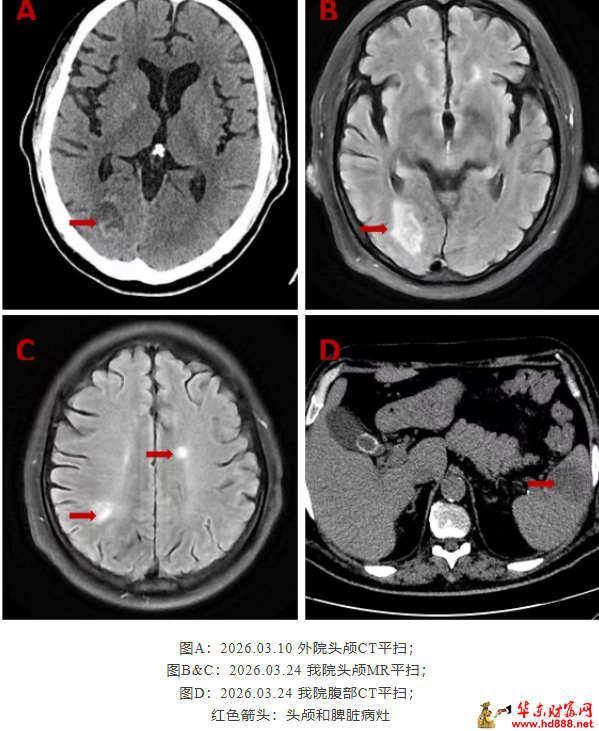

57岁的患者丁大叔,因“间断发热5月余”辗转多家医院,病情始终未能得到有效控制。长期的发热、精神萎靡、食欲减退,使其营养状态极差,体重明显下降,生命质量严重受损。患者先后被诊断为“骨结核”及多重病原体感染,包括罕见的龟分枝杆菌和戈登链球菌感染。 随着病情进展,患者心脏彩超提示出现感染性心内膜炎、二尖瓣赘生物形成及腱索断裂。 入院后,进一步检查发现,患者病情远比预想中复杂:不仅二尖瓣瓣叶存在赘生物及穿孔,主动脉瓣瓣叶上也存在赘生物及穿孔;同时,头颅MR 提示脑部存在三个可疑病灶(脑脓肿可能),腹部 CT提示脾脏低密度灶(脾脏脓肿可能)。

讨论专家一致认为:感染性心内膜炎时,心脏瓣膜上的赘生物由细菌、炎性细胞、纤维蛋白及血小板等成分构成,结构松散,极易脱落。脱落的菌栓随动脉系统循环播散,可栓塞全身多个器官。此患者头颅MR提示脑部三个病灶,腹部CT提示脾脏低密度灶,结合其血NGS检出戈登链球菌、骨穿检出龟分枝杆菌等病原学证据,高度提示为赘生物脱落所致感染性栓塞。 专家们严格遵循《感染性心内膜炎诊疗指南》,围绕抗感染方案、手术时机、手术方式及围术期管理进行反复论证。鉴于患者心脏结构损毁严重,存在脑脓肿、脾脓肿可能,继续内科抗感染治疗将面临赘生物脱落致反复栓塞甚至致命性卒中的巨大风险,因此选择亚急诊手术是权衡感染控制与栓塞风险后的最优策略。 最终,团队为患者制定了“强化抗感染+亚急诊手术+多脏器功能保护”的个性化综合治疗方案。